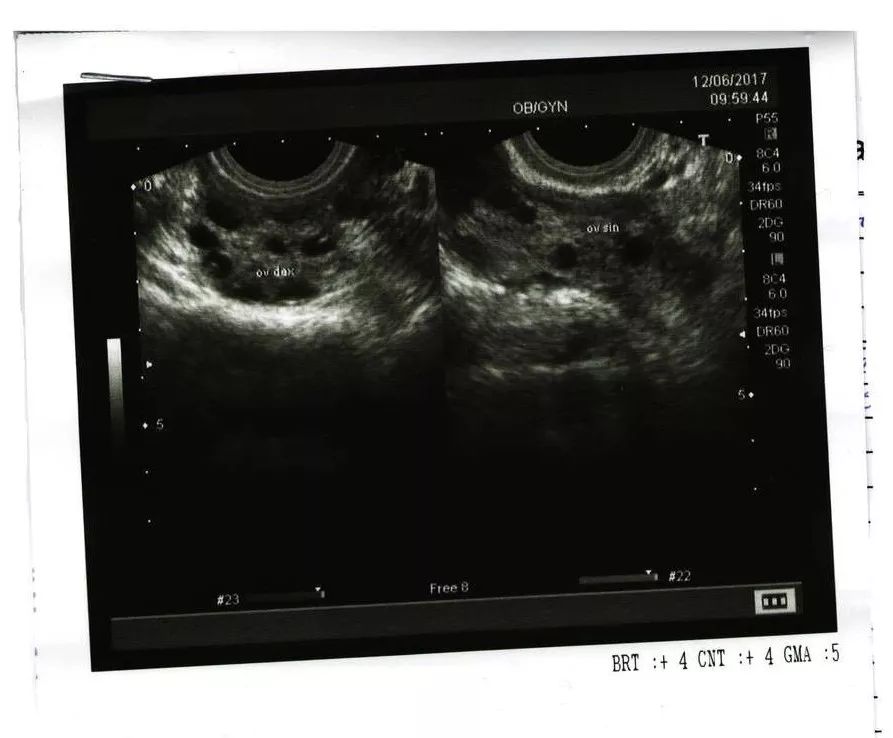

女性在做子宫附件B超的时候,医生看到一侧或双侧卵巢中,直径为2~9毫米的卵泡≥12个,和(或)卵巢体积≥10毫升,就会下卵巢多囊性改变的诊断。

在卵泡的募集、选择期做B超,很有可能就会在卵巢中找到12个以上直径为2~9毫米的卵泡;而且精神压力比较大,情绪不稳定,导致内分泌紊乱、月经失调,也可能会出现一过性的卵巢多囊样改变。

有研究表明,6%~25%的正常女性,卵巢可呈多囊性改变。而且,要是你的月经周期比较规律,那就更不用怕多囊卵巢综合征了。

多囊卵巢综合征(PCOS)是一种以雄激素过高的临床或生化表现、稀发排卵或无排卵、卵巢多囊改变为特征的病变,不是光通过B超就能确诊的。

2011年,中华医学会妇产科学分会妇科内分泌学组制定了“中国PCOS标准”。这个标准,把“月经稀发或闭经或不规则子宫出血”定为诊断多囊卵巢综合征的必须条件。虽然B超诊断出卵巢多囊性改变,但是有规律的正常月经,也不能诊断为多囊卵巢综合征。